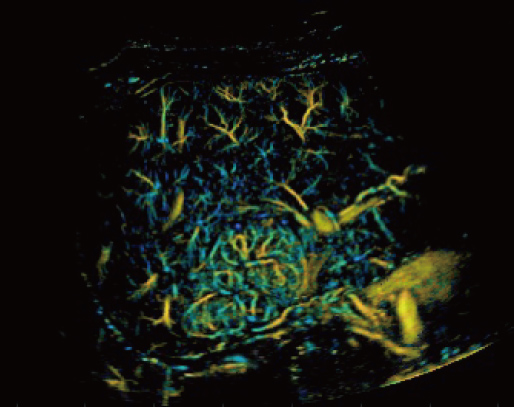

Dotato di un'ampia gamma di tecnologie di imaging innovative, Resona A20 supporta i medici nella ricerca clinica all'avanguardia. La Super Resolution CEUS (SR CEUS) rivela i dettagli della perfusione sanguigna a livello di micron, aiutando i medici nell'esplorazione delle prime alterazioni microcircolatorie nelle lesioni. Inoltre, la visco-elastografia STVi, una tecnica innovativa per la valutazione della viscosit├Ā dei tessuti, dimostra un grande potenziale per gli studi sulle malattie croniche del fegato e sui tumori.

Grazie alla piattaforma AIT, Resona A20 offre una soluzione integrata completa per l'imaging a super-risoluzione, una capacit├Ā finora difficile da raggiungere. La SR CEUS rivela i dettagli intricati del microcircolo delle lesioni a livello di micron, favorendo gli studi di perfusione microcircolatoria in oncologia.

Risoluzione a livello di micron

Capacit├Ā di rilevamento microvascolare

Iperplasia nodulare focale | Mappa densit├Ā

Iperplasia nodulare focale | Mappa direzione

Iperplasia nodulare focale | Mappa velocit├Ā